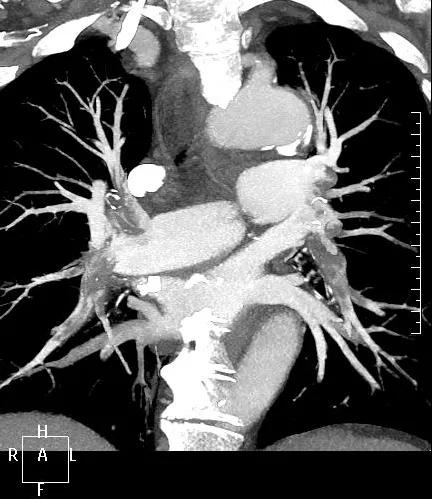

近日,一名港胞翁阿姨在我市突發(fā)急性肺栓塞,生命垂危。市二院在接到120出車指令后,迅速響應,患者入院后開通綠色通道,經(jīng)急診科、心內(nèi)科、介入科、重癥醫(yī)學科等多學科專家開展聯(lián)合會診,并于當晚9點行“下腔靜脈、肺動脈造影+導管溶栓+濾器植入術(shù)”,患者終于轉(zhuǎn)危為安,經(jīng)后續(xù)治療與精心護理,病情逐漸穩(wěn)定,現(xiàn)已轉(zhuǎn)入普通病房。